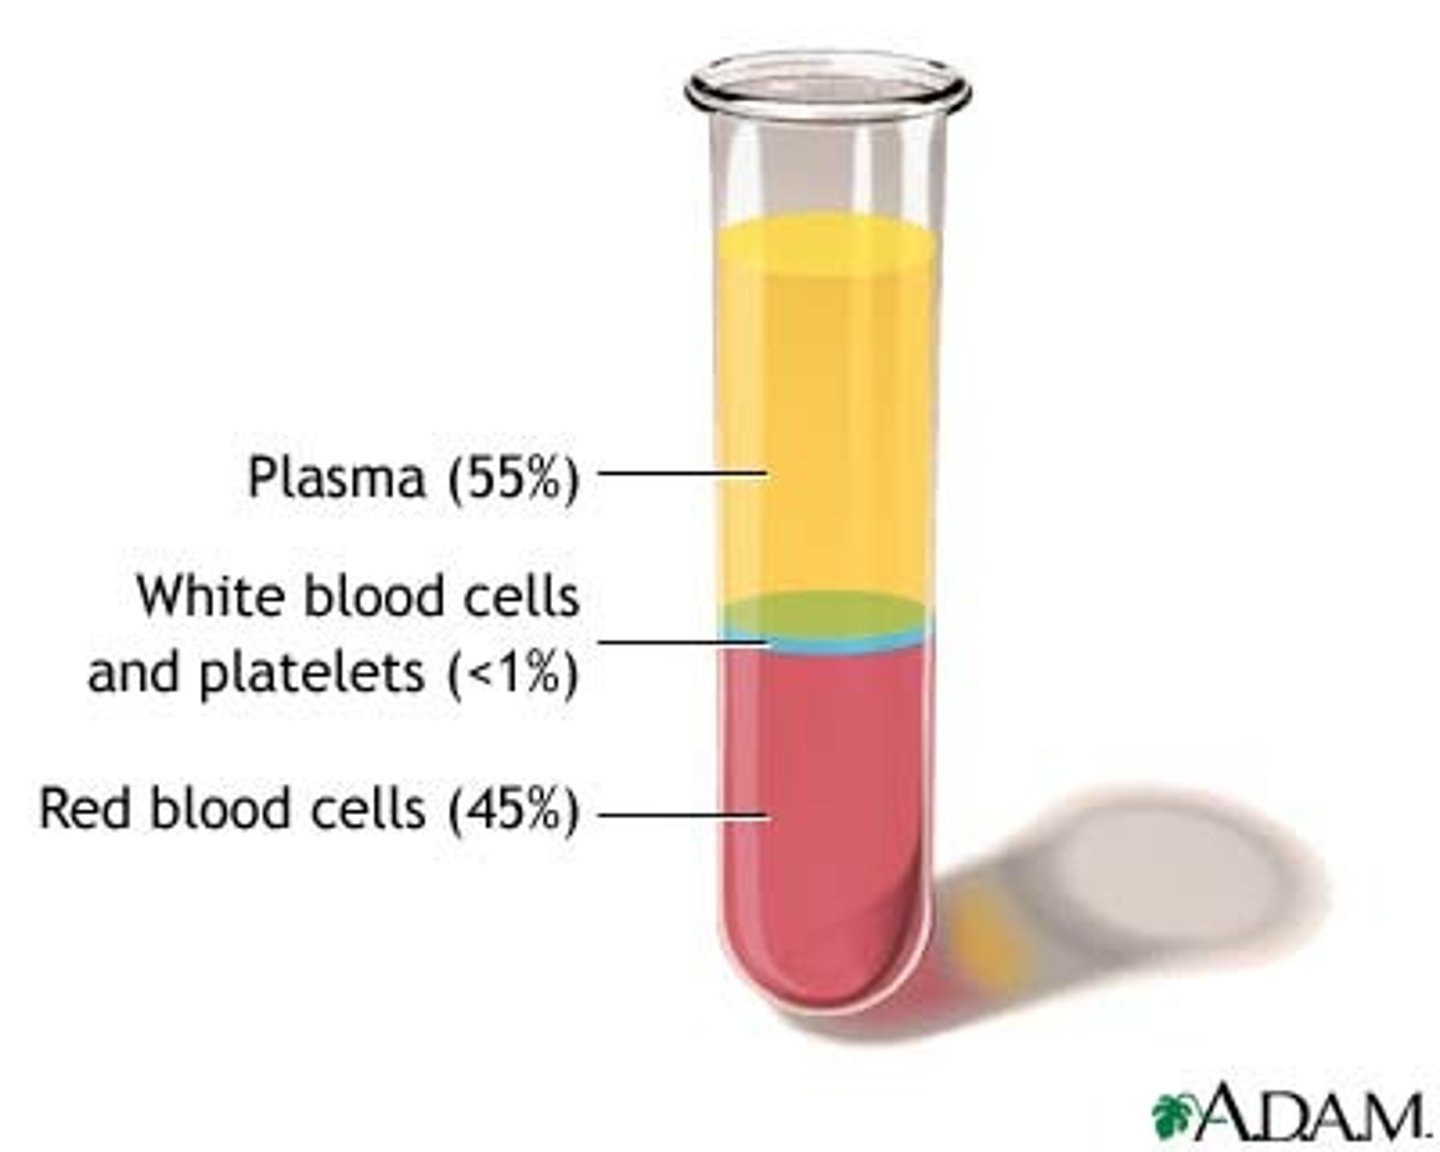

What is the cellular component of blood?

Erythrocytes, leukocytes, thrombocytes (45% of blood)

What is blood plasma?

Liquid part of blood, mostly water and proteins (55% of blood)

Blood fractionation

The process of separating it into its component parts using a centrifuge